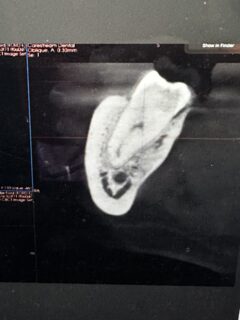

This is why we have a CBCT scanner - it tells us exactly where nerves are in relation to the tips of the roots..... planning is essential for these cases